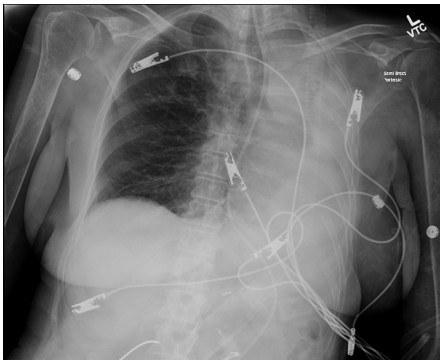

MRI Brain and c spine without acute abnormalities, b12, HIV and TSH within normal limits. Chest X Ray shows left lung atelectasis with ipsilateral mediastinal shift.